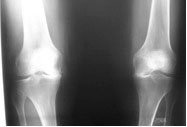

Of the realignment osteotomies around the knee 80% consist of high tibial osteotomy (also known as proximal tibial osteotomy, opening wedge, or valg-ising osteotomy) for varus osteoarthritis where the knee is abnormally bow-legged like in the gentleman below. In a high tibial osteotomy (HTO) the bone cut is at the upper ('high' or 'proximal') end of the tibia bone (shin bone).